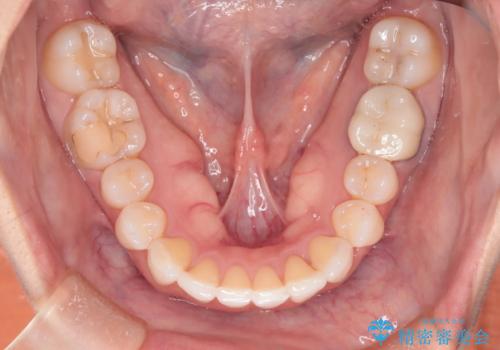

- 前歯のガタつき、変色を主訴に来院された患者様です。術前診査のCT撮影にて、変色した前歯の根の先に病巣があることが判明しました。そこで、マウスピースによる矯正治療と、前歯の根管治療、かぶせ物のやり直し治療を並行して行いました。

一般的に矯正専門歯科では、矯正以外の口腔内管理はほかの歯科へお願いされることが多いです。当院では、虫歯治療や根管治療の知識が豊富なドクターが矯正治療を担当いたしますので、安心して通院していただくことができます。